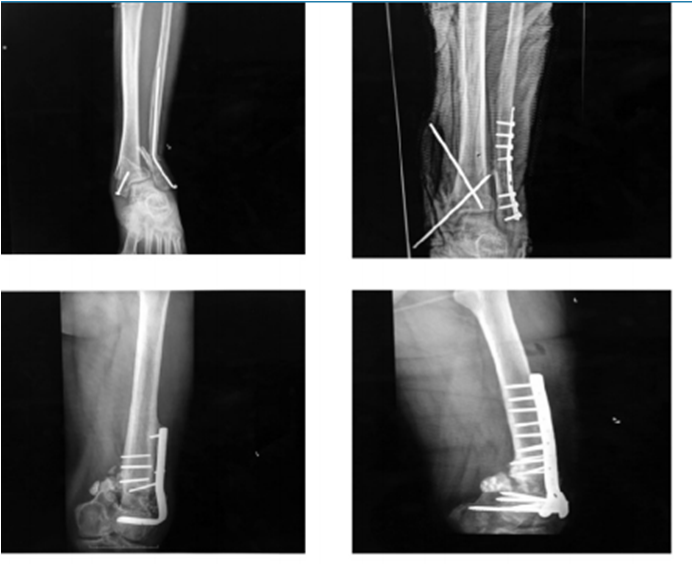

· 3 fracturas de calcáneo estabilizadas con placa LAMBDA utilizándose en una 15cc y en dos 30 cc del aloinjerto.

· 5 pacientes con pseudoartrosis, 3 correspondientes a meseta tibial a quienes se realizó osteosíntesis con placa de soporte en L y aloinjerto de chip de esponjosa 50 cc, 2 de fémur distal resueltas con placa condilar bloqueada con 60 cc de chip esponjosa y un paciente con fatiga de material de osteosíntesis (Fig. 4 y 5).

Las fracturas de meseta tibial, calcáneo y fémur distal presentaron una media de hospitalización de 12 días, se logró la consolidación en 90%, el tiempo promedio fue de 8 meses (4 -9 meses). En uno de los casos se realizó una reintervención quirúrgica por mala técnica.